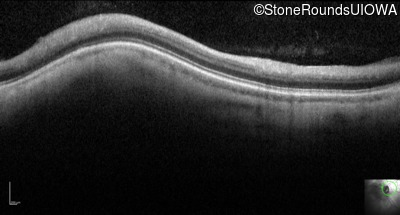

Case Level Images